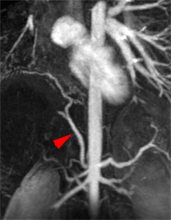

L’atteinte cardiaque peut se faire par propagation de voisinage en cas de tumeurs bronchiques ou médiastinales (A), par voie hématogène en cas de métastases à distance (cf: métastase intra-myocardique d’un cancer ORL illustrée en B), par voie lymphatique ou veineuse prenant les cavités cardiaques droites comme dans les exemples ci-dessous d’extension d’un EOA utérin enclavée dans l’infundibulum (C) ou de tumeur de Grawitz envahissant l’oreillette droite (D).